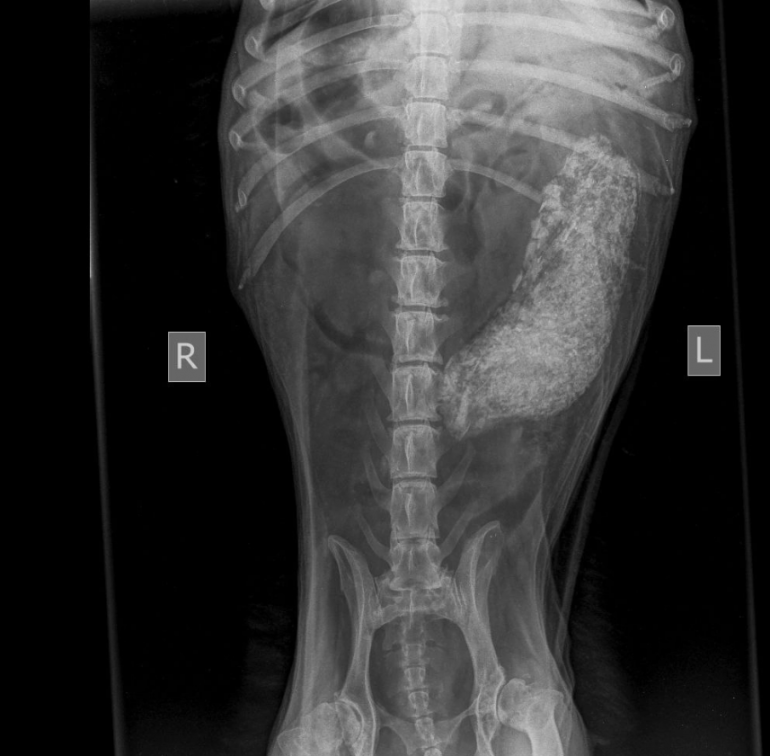

- Осмотрев животное, было принято сделать рентген брюшной полости на наличие инородного тела, так как признаков инфекции у собачки не было. К сожалению опасения инородного тела подтвердились, и мы в срочном порядке прооперировали Найду, - рассказали в ветклинике.

Операция прошла успешно. Инородным телом оказалось большое скопление травы, мелкие камни и целлофановый пакет – собака съела всё, что можно и что нельзя.